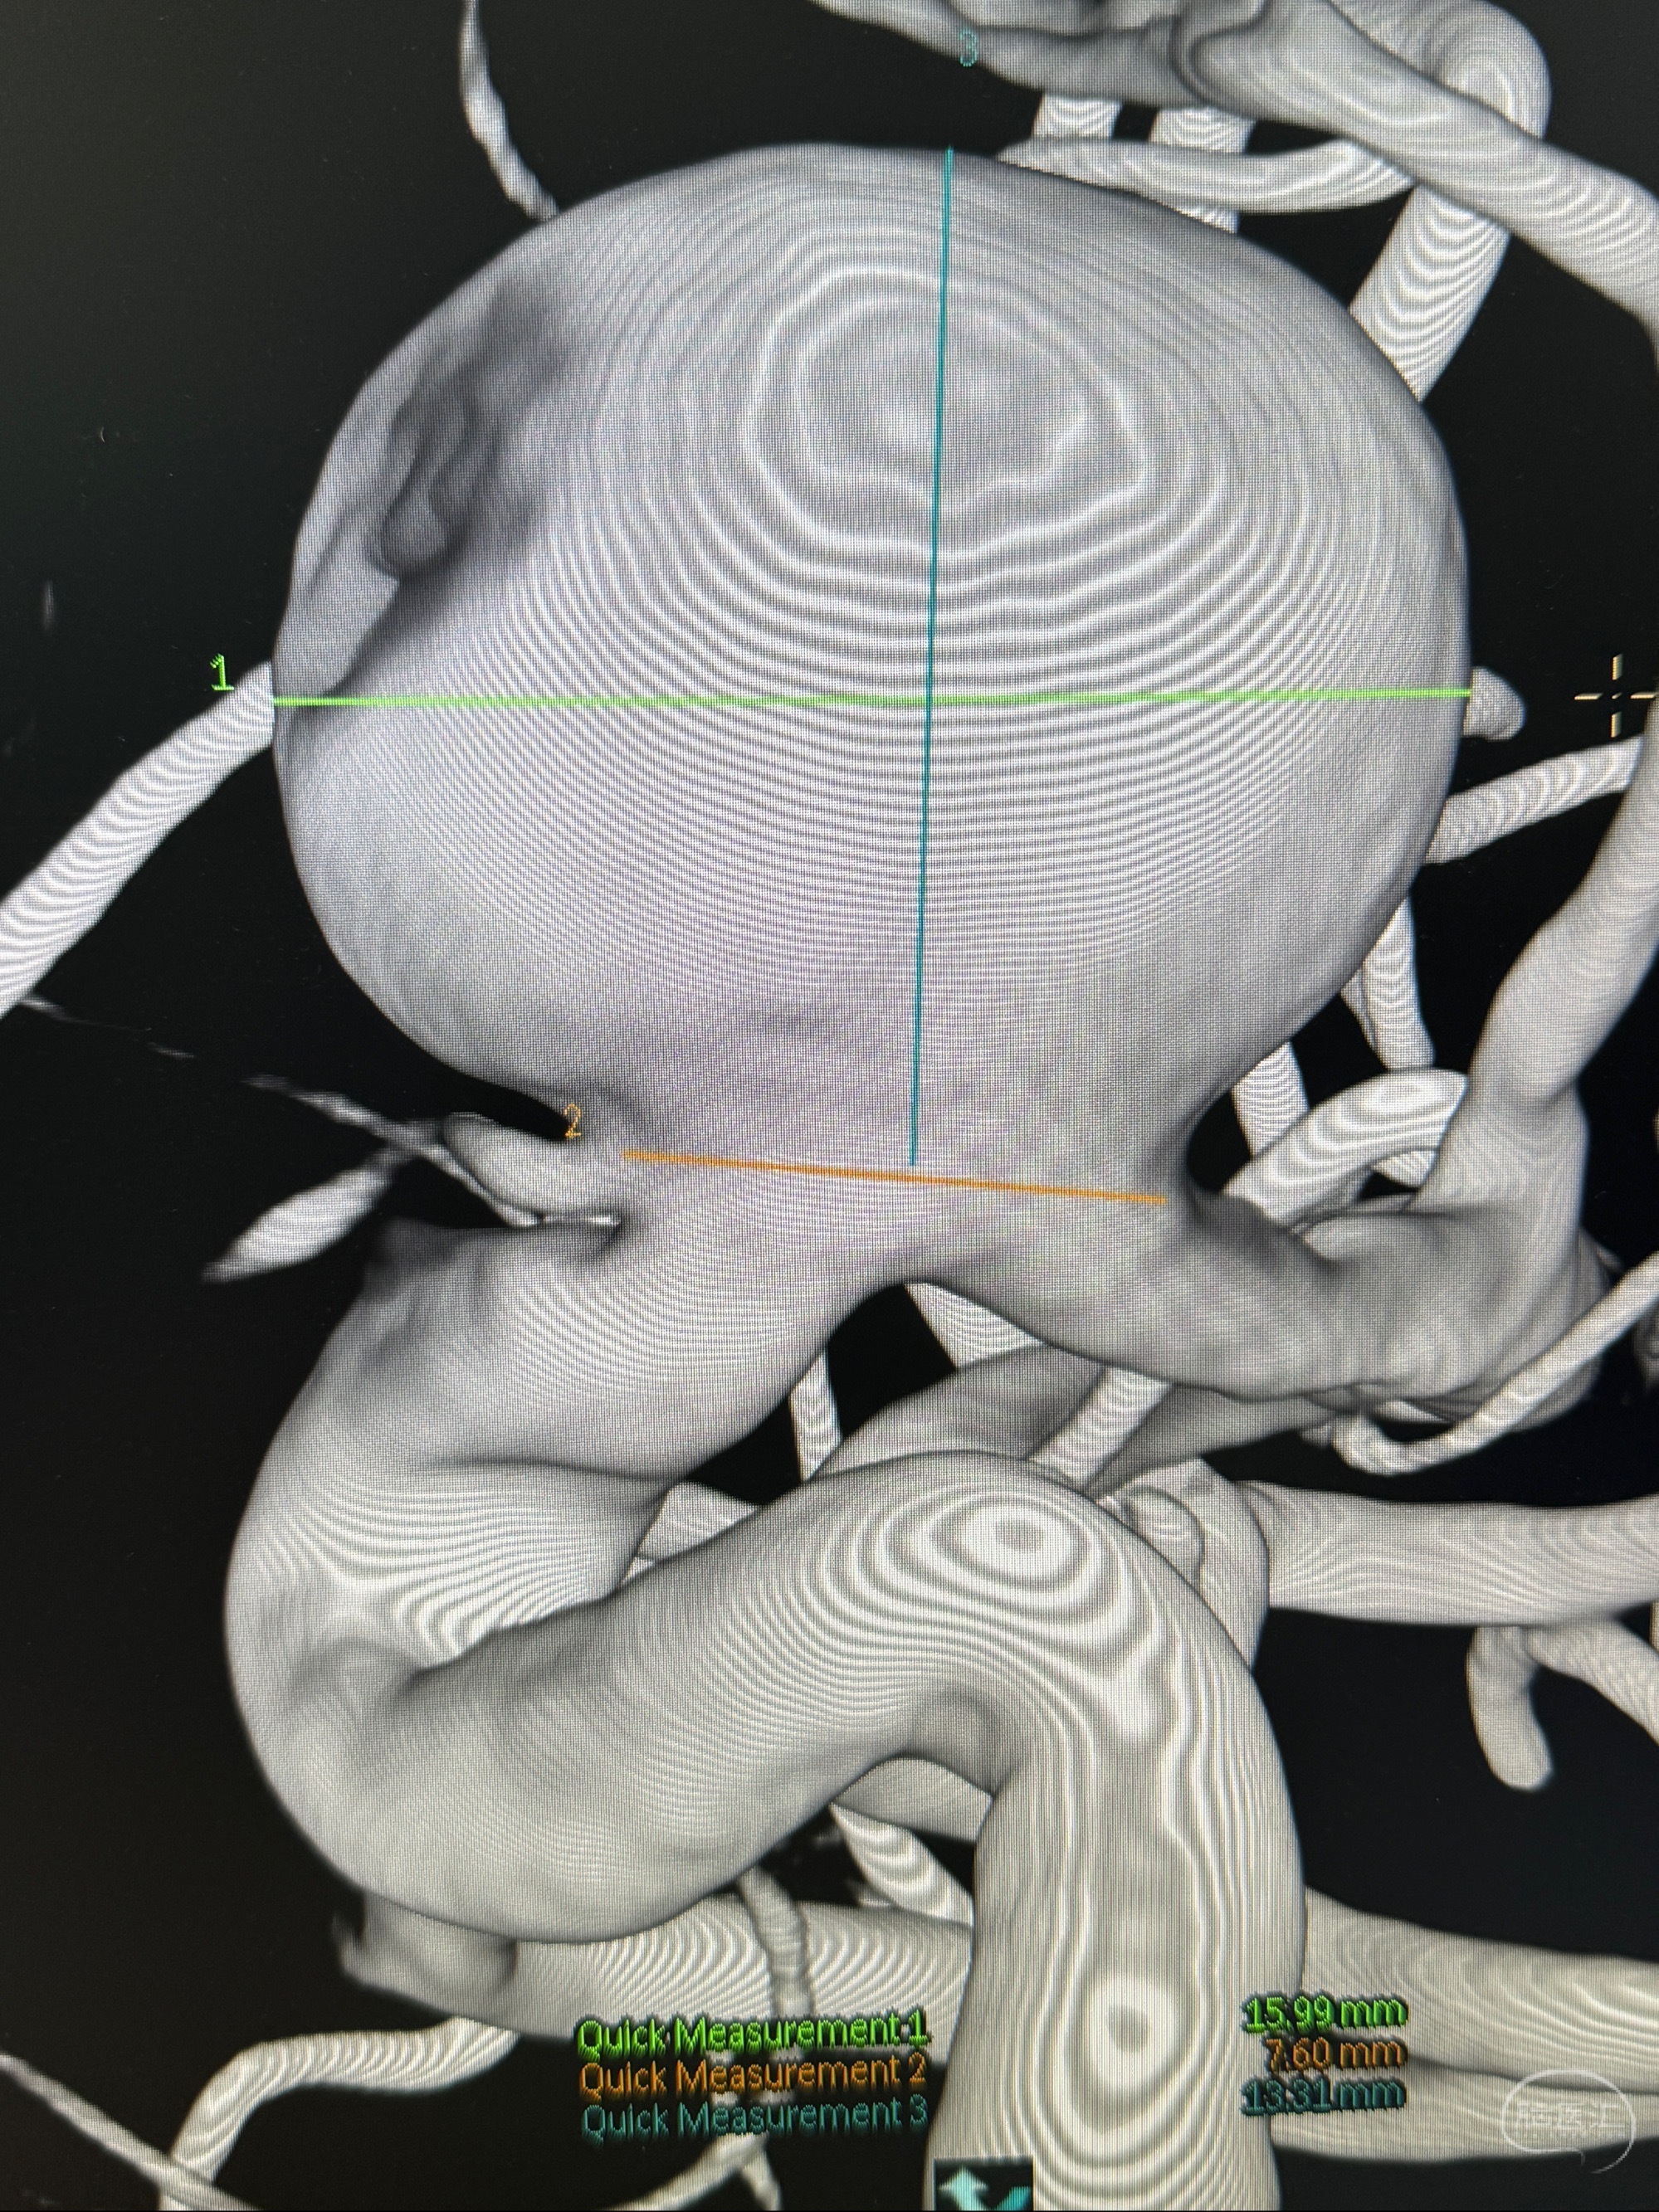

旋转3D展示动脉瘤局部的血管构筑

测量动脉瘤的大小:16*13.8*7.6mm大小,较原先变大,考虑双抗后瘤内血栓溶解可能